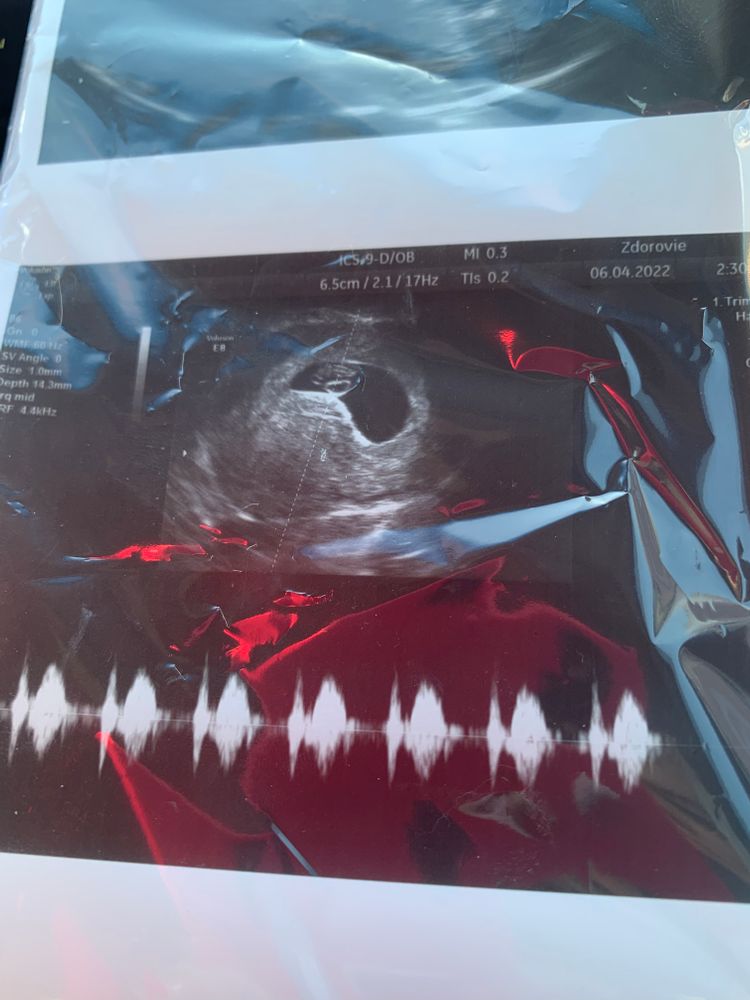

29 дпп 💓узи🤰🤰🤰

Всё о нашей беременностиВот и съездили мы на второе узи 🤗 все хорошо , сердечко 💓 стук стук 😍 ох этот звук не забываем 🥲

пя соответствует сроку , а вот эмбриончик обгоняет на 3 дня по размерам , успокойте меня 🙏 и скажите что это не страшно